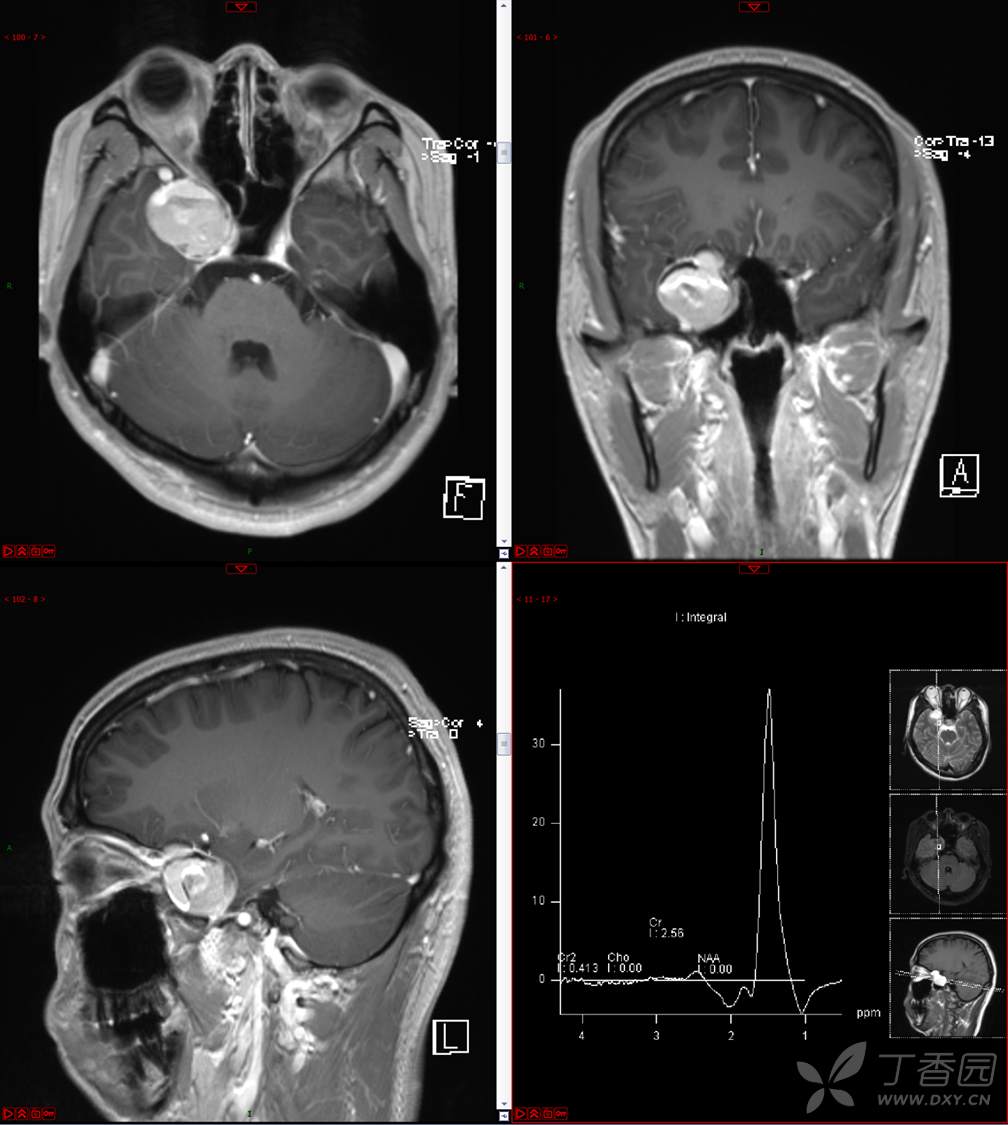

【影诊笔记534】青年男性,视物模糊就诊,CT、MRI、MRS齐全,请分析~~~

主 诉:视物重影5天。

现病史:患者5天前无明显诱因出现视物重影,表现为右视时视物成双,无头痛、头晕,无恶心、呕吐,无面部麻木、饮水呛咳等,于当地医院就诊,行颅脑MR示“颅内占位性病变”,现为求进一步治疗来诊。患者病来精神可,饮食、睡眠正常,体重无明显变化。